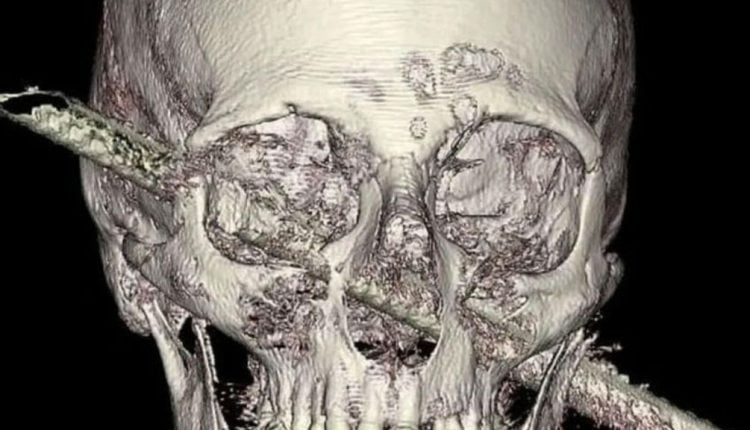

وعلى الرغم من ثقب السيخ المعدني رأس عبدالرحمن بالقرب من أذنه اليمنى حتى أعلى عينه اليسرى مباشرة، إلا أنه لم يشعر بالألم في تلك اللحظة وحتى بعد نقله الى المستشفى.

وفور وصوله المستشفى وجد الجراحون أن السيخ المعدني لم يخترق اثنين من الشرايين الرئيسية التي تعمل على إيصال الدم للدماغ، ولكن وضع الأطباء في قرار صعب وهو الآثار المترتبة على محاولة إزالة السيخ المعدني من رأسه.

واستمرت عملية إزالة السيخ المعدني من رأسه عدة ساعات وذلك بعد التأكد من انه بصحة جيدة، ولكن أجرى الأطباء عملية جراحية ثانية استمرت لمدة 10 ساعات لمحاولة وقف النزيف وتمت باستخدام كاميرات تم إدخالها من الأنف، ونجح الأطباء في إتمام العملية الجراحية.